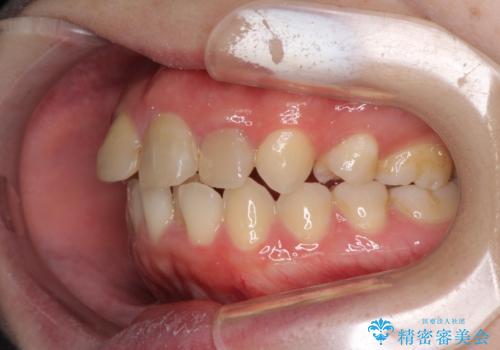

抜歯矯正の後戻り インビザラインによるオープンバイトの再矯正

- 以前矯正治療をされていましたが、後戻りが起きたことを気にして来院された患者様です。

上下前歯のオープンバイトを改善するため、インビザラインにて治療を行うこととしました。

外食が楽しみである患者様だったので、インビザラインによる治療期間は我慢の時期であったようです。

自己管理を徹底していただいたので、1年程度で治療を終えることができました。